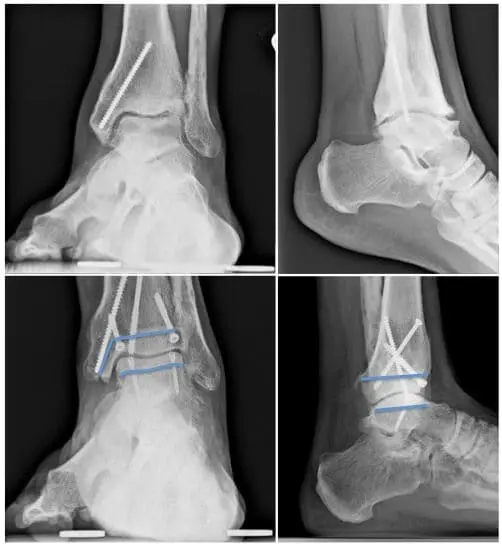

Arthrodesis: In advanced cases of osteoarthritis or arthritis, this remains seen as the gold standard treatment. The joint is fixed into its neutral position by means of open surgery or arthroscopy. The advantages are that it is a very reliable operation with clearly positive results over the years, and that it is a single procedure. Disadvantages are the prohibition to lean on the ankle and a plaster for 2 months after the operation, but mainly the fact that after an indefinite period (20-30 years), degenerative disorders may occur in the adjacent joints. These should take over part of the mobility of the ankle.